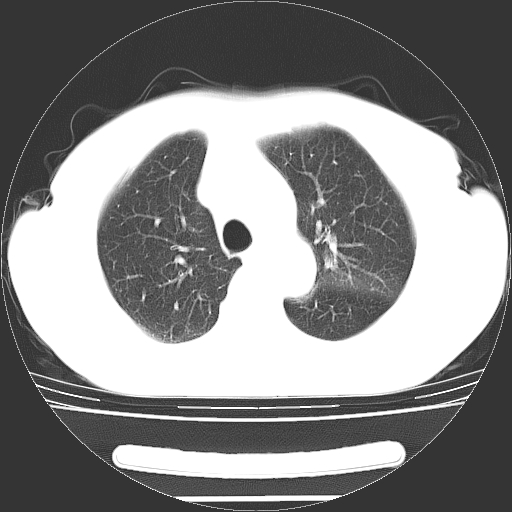

首先考虑为脾脏明显肿大,内可见多量弥漫性低密度区,边界不清,考虑脾占位性病变,以转移瘤及淋巴瘤可能性大.

其次考虑肺内病灶如恶性肺间质肉瘤,建议增强及胸腹部扫描

影像诊断重在定位定性,首先应先定性,其次才能定性。本病例从最上层面看病变与胸壁关系密切,局部胸膜稍增厚,左肺受压;病变最低层面未扫完。可以有三种情况:1、肺内病变?2、胸壁病变?3、内脏异位(巨脾可能)?建议增扫上腹部并增强检查。